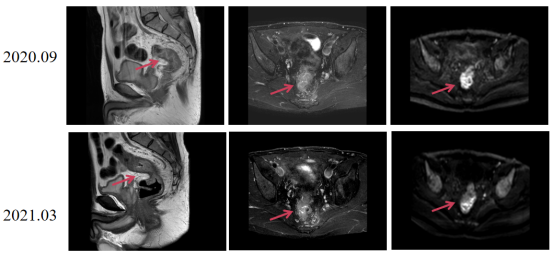

2020.09.23 直肠MRI影像:直肠异常改变,符合直肠Ca。发现直肠癌距肛门位置小于10cm。

image.png

图1 初诊时直肠MRI

图4 影像评估提示直肠肿瘤较前缩小